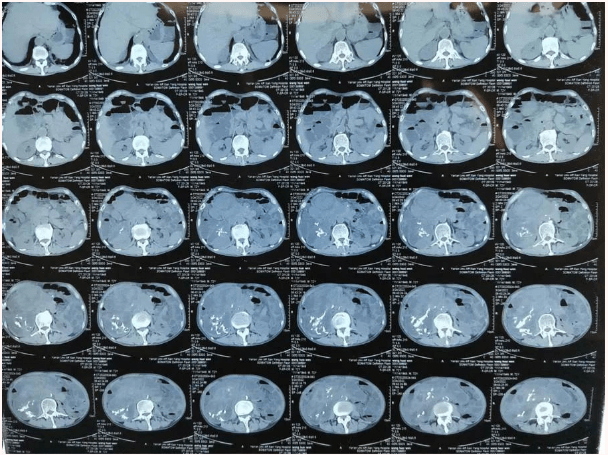

患者王大爺,男,72歲,發(fā)現(xiàn)腹腔腫物10余年,近兩年來患者雙下肢乏力、貧血,依靠間斷輸血維持著正常生活,出現(xiàn)頭昏,行動(dòng)困難,腹部疼痛及便血慕名來我院就診。入院后查體評(píng)估患者年齡大,體質(zhì)差,嚴(yán)重貧血,肺部感染及腸梗阻征象,腹部增強(qiáng)CT檢查提示腹膜后巨大腫瘤,長(zhǎng)徑超過30厘米,占據(jù)大部分腹腔,并可能存在雙原發(fā)腫瘤。